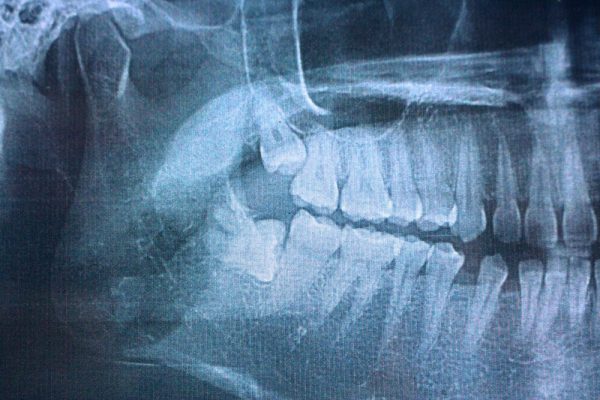

- Advanced Imaging: Panoramic X-rays or 3D imaging provide detailed views of tooth positioning, root development, and proximity to important structures like nerves and sinuses.

Types of Wisdom Tooth Impaction

Understanding different types of impaction helps patients recognize their situation and treatment needs:

Common Impaction Categories

Soft Tissue Impaction: The tooth has enough space to emerge but remains partially covered by gum tissue, creating pockets where bacteria and food particles accumulate, leading to infection and gum disease.- Partial Bony Impaction: The wisdom tooth is partially blocked by bone, preventing complete eruption and often causing the tooth to emerge at an angle that creates cleaning difficulties and potential damage to adjacent teeth.

- Complete Bony Impaction: The tooth remains completely encased in jawbone and cannot emerge naturally, often requiring more complex surgical procedures to access and remove safely.

Positioning Problems

Horizontal Impaction: The tooth lies sideways beneath the gum line, often pressing against the roots of the second molar and potentially causing significant damage if not addressed promptly.- Vertical Impaction: The tooth is positioned correctly but lacks adequate space to fully emerge, often causing crowding and pressure against the second molar.

- Angled Impaction: The tooth is tilted forward or backward, creating challenges for both oral hygiene maintenance and surgical removal procedures.